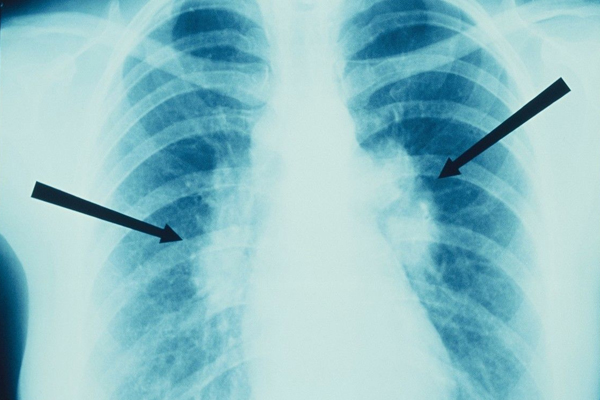

从光滑程度看,良性的结节外形是比较光滑的,并且边界清晰;恶性的结节表面粗糙,边界不清晰。从形状看,良性的肺结节通常是圆形或是椭圆形的;而恶性的结节很少有这两种形状,大多是葫芦状的。从长大的速度来看,良性的结节几个月或是几年可能变化都不是很大;恶性结节很可能会随着时间的变化而慢慢长大。从软硬程度来看,如果是质地较硬的结节通常就是良性的;而恶性结节不会完全钙化的,质地不是很硬。从外侵的迹象来看,良性的结节通常不会有外侵的情况发生,不影响周围的器官组织;恶性结节很大可能会入侵到周围的组织,影响到其它的组织。